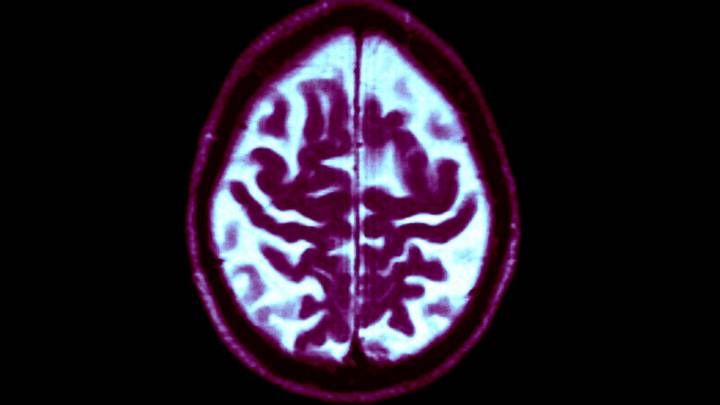

Texas voters Tuesday approved Proposition 14, which creates a state-funded dementia research facility and sets aside money aimed at prevention of the disease.

SJR 3 authorizes the state comptroller to set aside $3 billion from the state’s general fund to create the Dementia and Research Institute of Texas. The measure also provides funding for research and prevention efforts around dementia, Alzheimer’s disease and Parkinson’s disease.